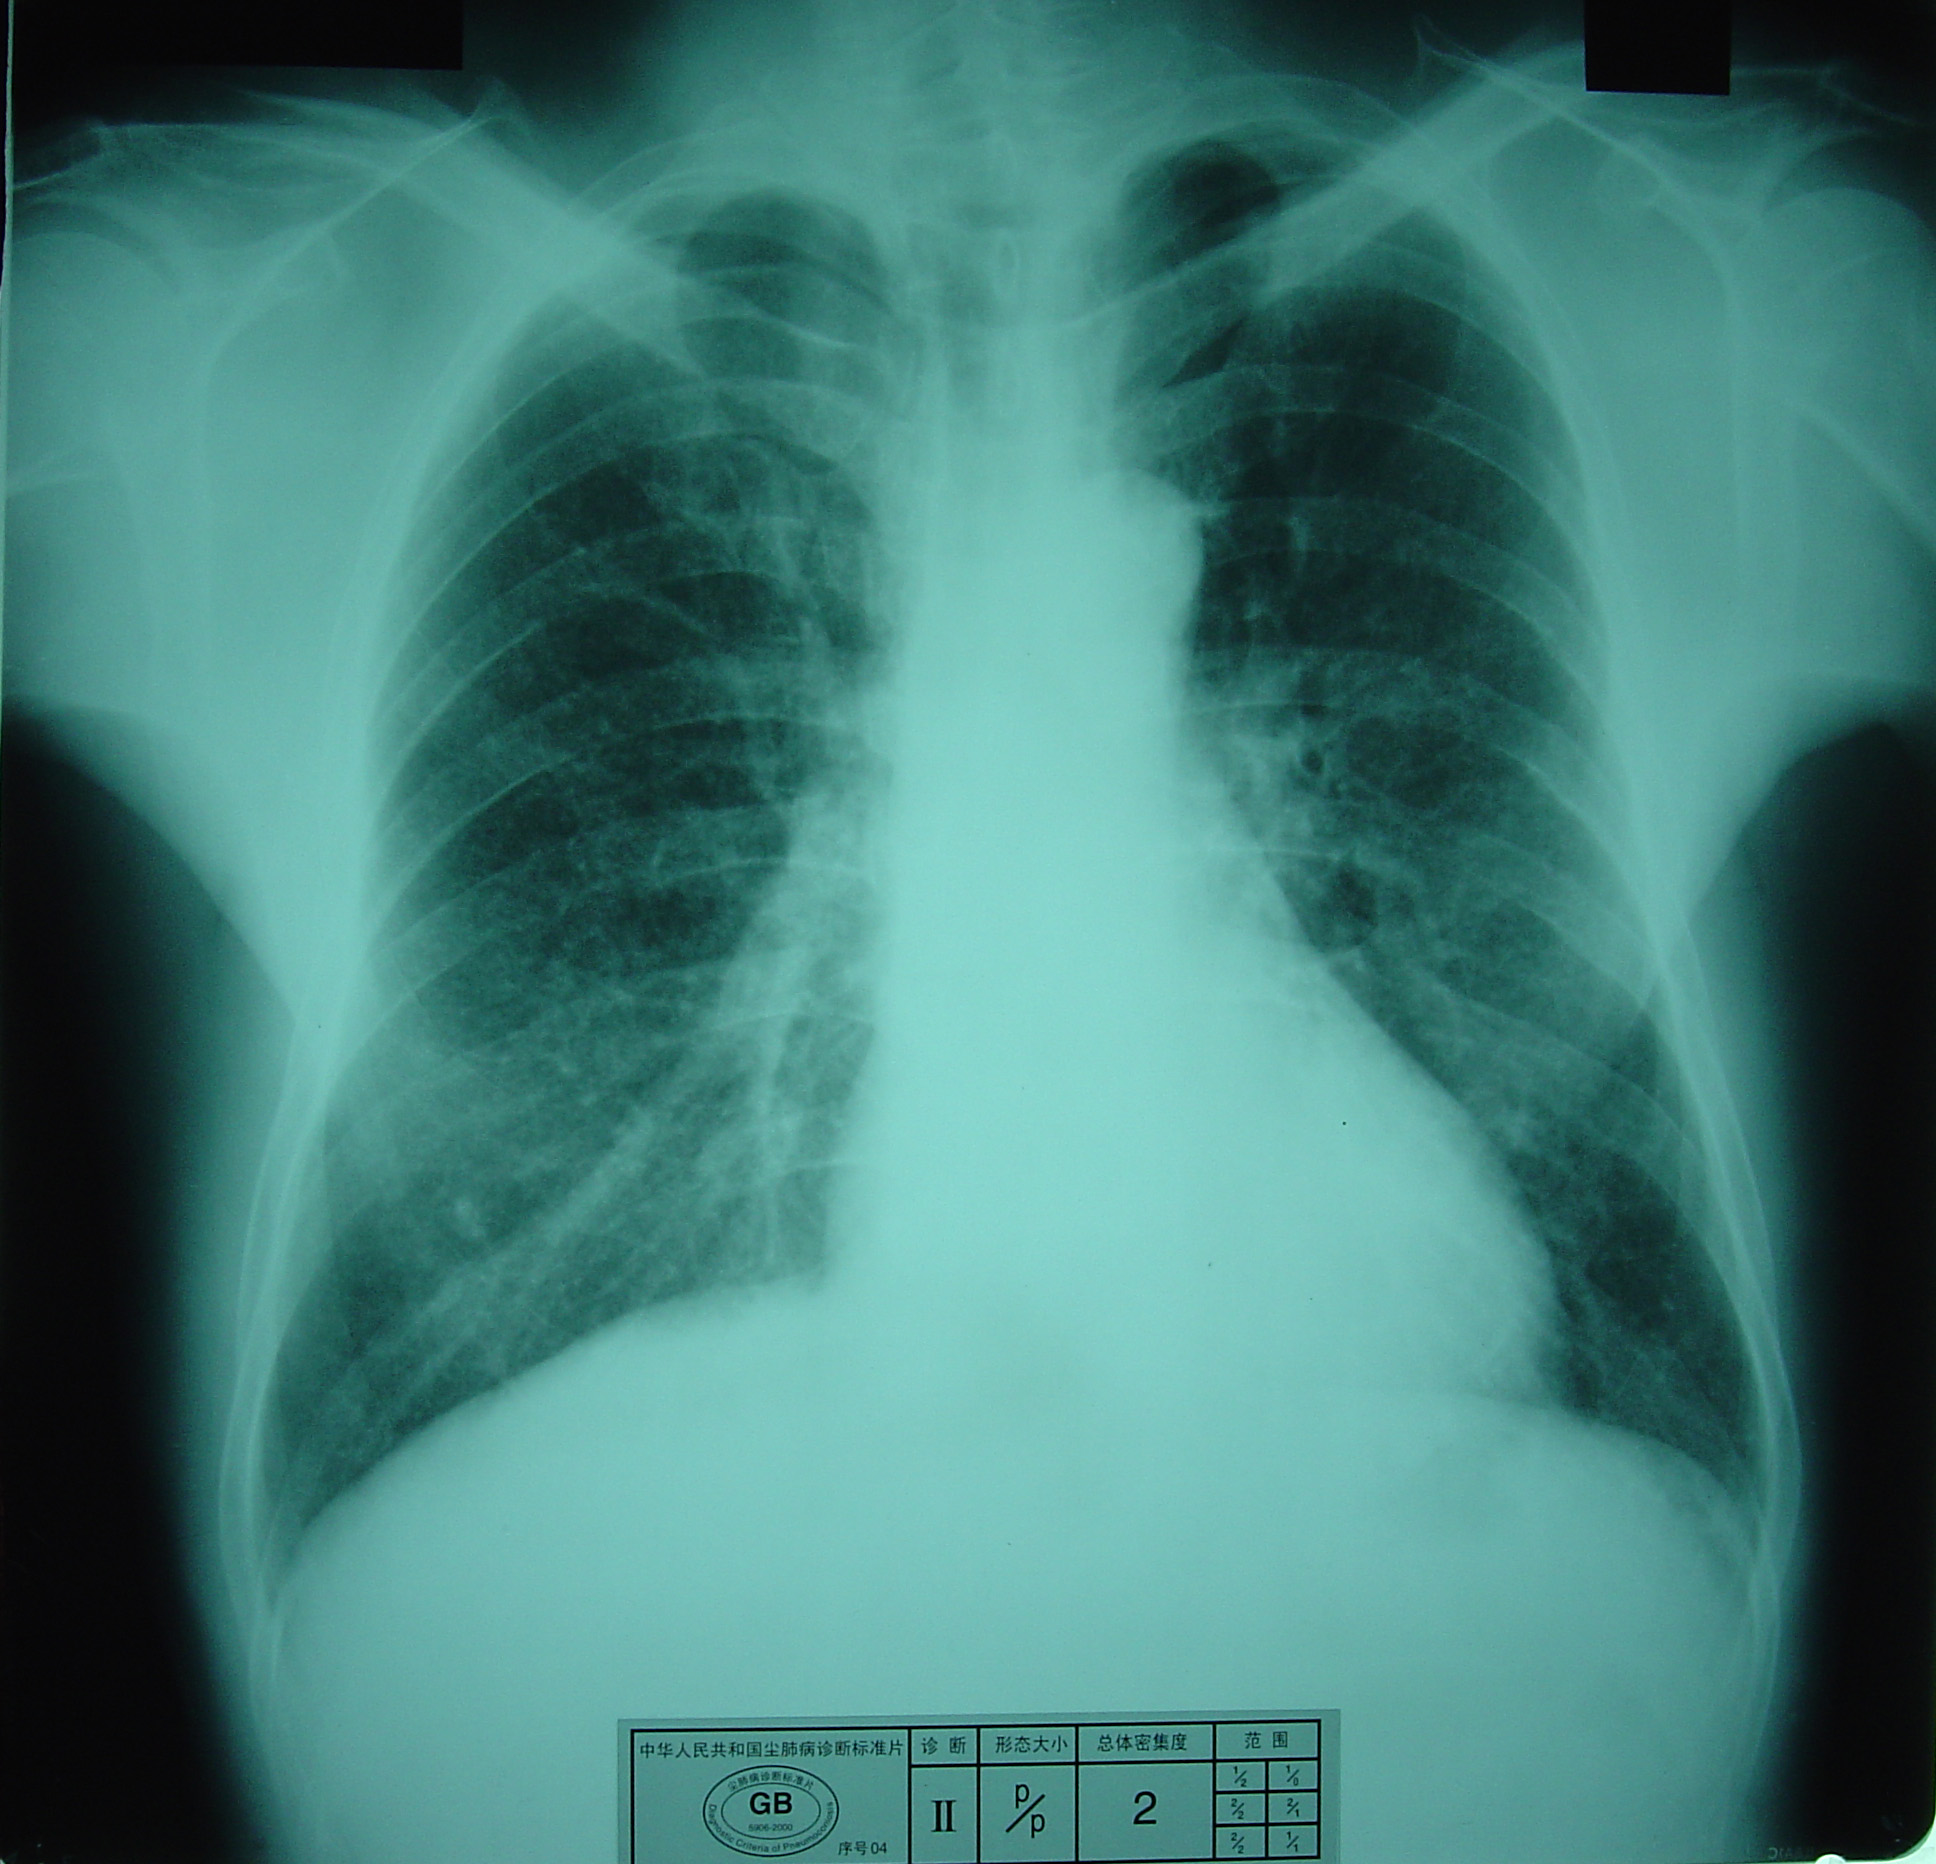

(2)X射线胸片表现:矽肺X射线胸片影像是肺组织矽肺病理形态在X射线胸片的反映,是“形”和“影”的关系,与肺内粉尘蓄积、肺组织纤维化的病变程度有一定相关关系,但由于多种原因的影响,并非完全一致。这种X射线胸片改变表现为X射线通过病变组织和正常组织对X射线吸收率的变化,呈现发“白”的圆形或不规则形小阴影,作为矽肺诊断依据。X射线胸片上其他影像,如肺门变化、肺气肿、肺纹理和胸膜变化,对矽肺诊断也有参考价值。在X射线胸片上,肺野内直径或宽度不超过10mm的阴影。小阴影按其形成分为圆形和不规则形两类。

1)圆形小阴影:是矽肺最常见和最重要的一种X线表现形态,其病理基础以结节型矽肺为主,呈圆或近似圆形,边缘整齐或不整齐,直径小于10mm,按直径大小分为p(<1.5mm)、q(1.5~3.0mm)、r(3.0~10mm)三种类型。p类小阴影主要是不太成熟的矽结节或非结节性纤维化灶的影像,q、r类小阴影主要是成熟和较成熟的矽结节,或为若干个小矽结节的影像重叠。圆形小阴影早期多分布在两肺中下区,随病变进展,数量增多,直径增大,密集度增加,波及两上肺区。

圆形小阴影(q类小阴影)

2)尘肺贰期:有下列表现之一者:

a) 有总体密集度2级的小阴影,分布范围超过4个肺区;

b)有总体密集度3级的小阴影,分布范围达到4个肺区。

尘肺贰期

尘肺贰期

尘肺贰期

尘肺贰期